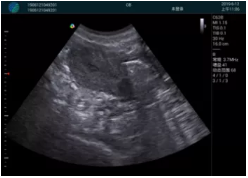

清晰顯示孕囊,通過軟件包計算孕齡7w+6d

M20實時引導,術中清晰顯示孕囊被破壞和抽吸針的過程,清晰顯示吸引針

抽吸結束后縱切子宮,孕囊已被完全抽吸,未見明顯殘留

橫切子宮,發(fā)現右側宮腔靠近宮角處有少許脫模樣殘留

M20引導下,抽吸針找到右側宮角處再次清掃

二次抽吸后再次進行超聲檢查,宮腔未見殘留,宮腔線清晰顯示